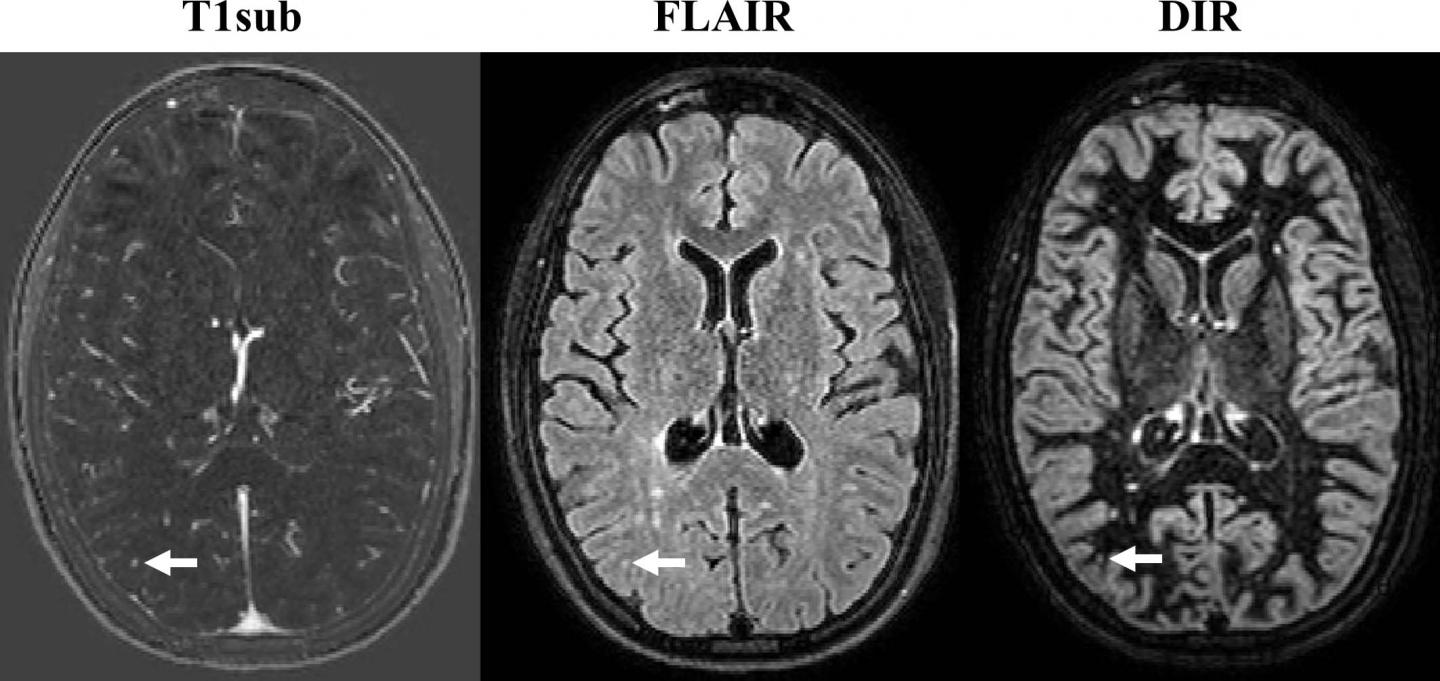

Quantitative MRI for Analysis of Active Multiple Sclerosis Lesions Can Ms Be Seen On Mri Without Contrast We recommend an initial cervical and thoracic spine mri with and without contrast along with brain mri in patients suspected of having ms, for. Typical ms lesions tend to be oval or frame shaped. Ms lesions can appear in both the brain’s white and gray matter. Research published in the journal radiology last march, titled “ accuracy of unenhanced mri. Can Ms Be Seen On Mri Without Contrast.

MRIBrain with contrast T1 showing multiple MS lesions, no contrast Can Ms Be Seen On Mri Without Contrast Mri scans can pick up these areas of damage, called lesions, in different parts. Ms lesions can appear in both the brain’s white and gray matter. Why are mri scans important for an ms diagnosis? Typical ms lesions tend to be oval or frame shaped. Research published in the journal radiology last march, titled “ accuracy of unenhanced mri in. Can Ms Be Seen On Mri Without Contrast.

Noncontrast MRI is effective in monitoring M EurekAlert! Can Ms Be Seen On Mri Without Contrast Ms lesions can appear in both the brain’s white and gray matter. Why are mri scans important for an ms diagnosis? Typical ms lesions tend to be oval or frame shaped. Ms activity appears on an mri scan as either bright or dark spots. Research published in the journal radiology last march, titled “ accuracy of unenhanced mri in the. Can Ms Be Seen On Mri Without Contrast.